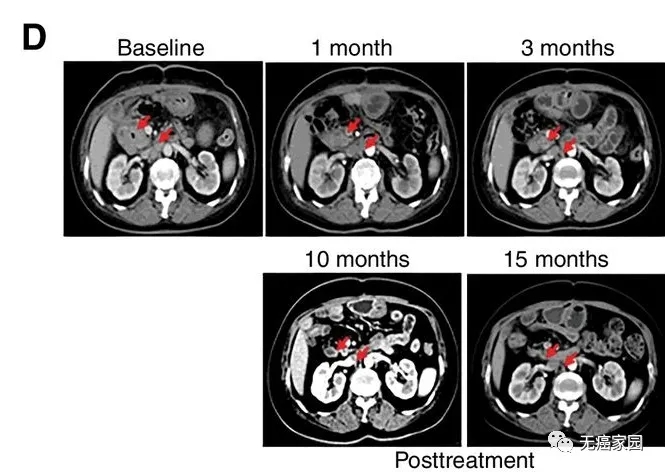

研究结果显示,17例患者可评估,其中1例胆管癌患者的肿瘤完全消失,截止到目前疗效已经保持了22个月,尚未发现疾病复发。10例患者疾病稳定,疗效保持2.5~15.5个月,中位无进展生存期为4个月。

CART-RGFR细胞治疗之前和1、3、10和15个月患者1的CT扫描图像。红色箭头表示原发肿瘤和腹膜后淋巴结转移。

在研究中有10例患者在化疗预处理中出现3~4级的副作用,经积极处理均可恢复正常。